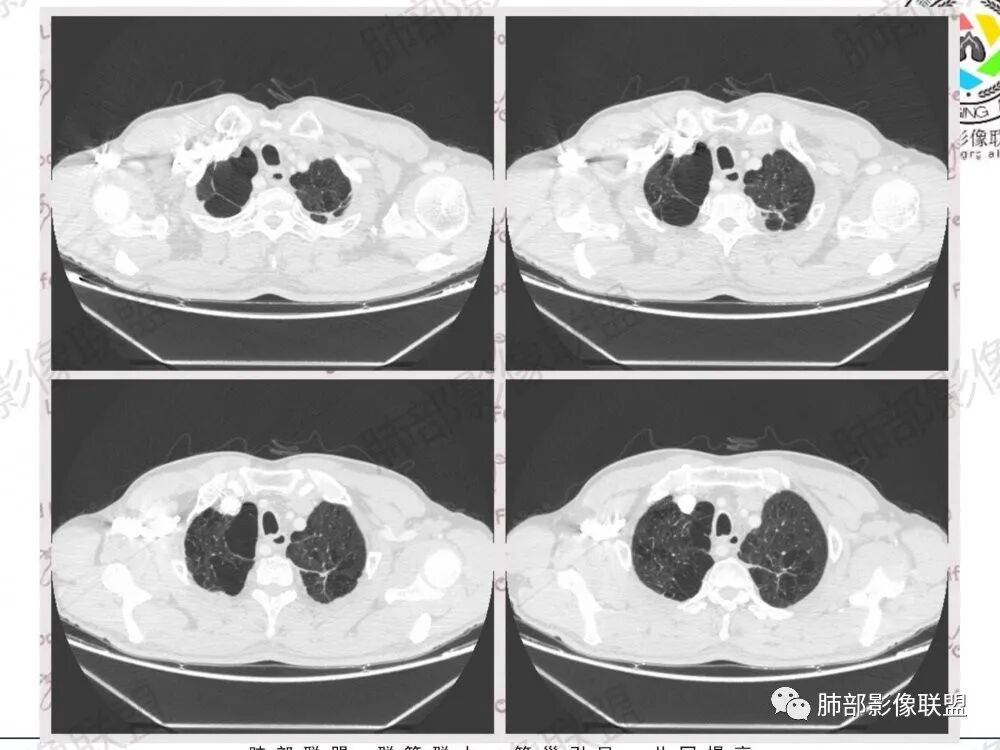

57岁男性,长期吸烟史,有血吸虫病史,有粉尘接触史。发现纵隔淋巴结肿大2年,声嘶伴咳嗽咳痰半月。两年前胸部CT见左上肺尖后段结节并肺门淋巴结肿大,治疗后左上肺结节消失。目前胸部CT:肺气肿,左上肺尖后段见条索影(原来结节治疗后的改变?),肺门、纵隔淋巴结肿大并融合,似见薄壁包膜样强化。考虑淋巴结结核可能性大,注意鉴别淋巴瘤、转移、结节病等。

中老年男性,长期吸烟,肺气肿明显,发现纵隔淋巴结两年了,声音嘶哑,病灶压迫喉返神经了?喉部有占位吗?左肺尖小片状病灶,周围多发长条纤维牵拉,胸膜增厚,纵隔及左肺门多发肿大淋巴结,增强后显示淋巴结融合且坏死明显,薄环状强化。如果是恶性肿瘤,小细胞癌或者鳞癌,肺内病变应该增大增多了;一元化我考虑纵隔淋巴结结核,左肺尖结核灶。

肺内好像就是慢阻肺痰栓

病史,吸烟老年男性,这是个不好的病史问题来了,原来有左上肺结节并淋巴结肿大,治疗后好了,现在又有淋巴结肿大

1.左肺门及纵隔见异常增大淋巴结,部分融合,不均匀轻度强化,未见明显坏死。

别忘了,患者左肺上叶那个略显饱满的的小结节,有理由相信那是发源地。

声音嘶哑、左侧声带固定等是左肺上叶肺癌最具代表性的临床表现之一,有经验的耳鼻喉科医生常会因此要求患者排查肺部。

左肺上叶肺癌在主动脉窗附近侵犯阻击远道而来的左侧喉返神经是其常见套路。

临床实践中,除肺癌外,较少其他病灶能够造成左侧声带麻痹。

注意是左侧喉返神经!右侧喉返神经并未绕行胸廓入口以下。